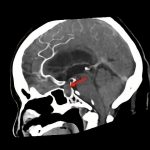

断層撮影